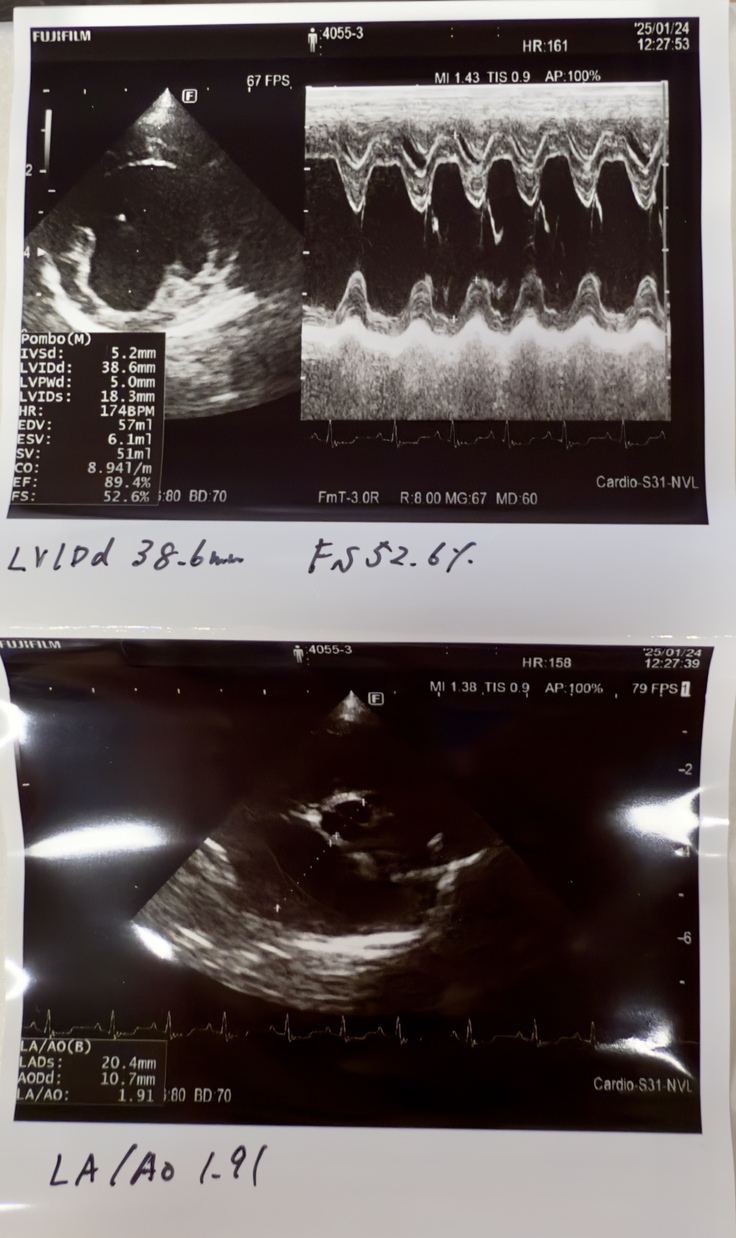

⬇️はシフォンの僧帽弁の逆流を状態を現す心エコーの画像です。(A病院での検査)

分かりにくいですが以下のことが分かります。

※シフォンの心臓は血液の流れを一定方向に保つための僧帽弁がしっかり開閉していないので、血液の逆流や漏れが起きており、心臓に負担がかかり心肥大の状態にあります。